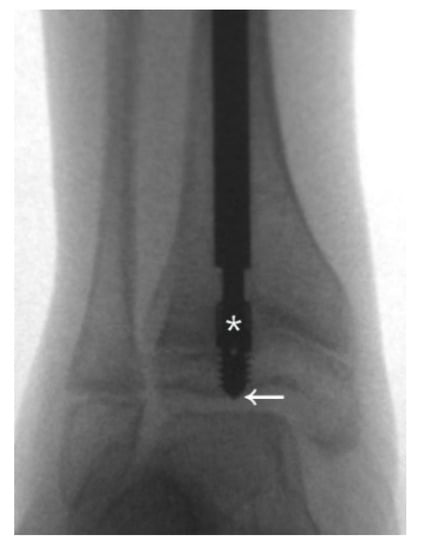

In a case of a 4-year-old female with type III OI (Figure 1), the position of the male component was quite central in the distal epiphysis on both anteroposterior and lateral views. However, there was insufficient purchase of the male component tip (Figure 1a). If the threads end just around the physis instead of beyond it (Figure 1b), distal dislodgement would occur along with growth of the limb (Figure 1c). However, this raises the question of how to ensure sufficient depth of the male implant intraoperatively. We suggest the following steps: First, center the male component at the center of the distal epiphysis as far as possible so that the thickest epiphysis is purchased. The thread of the male component needs to be fully submerged into the epiphysis, and the flange of the nail must exceed the physis, or at least stop at the level of the physis. If the distal epiphysis of the tibia is small, the tip of the nail may reach the subchondral area to ensure that the whole thread goes through the physis (Figure 2). Since the distal epiphysis of the femur is larger than the distal epiphysis of the tibia, there is a relatively lower risk of distal dislodgement in the femur (tibia 4, femur 1 in our series) due to sufficient distal purchase.

Migration of the male component is common in the tibia due to an almost empty epiphysis [18,19]. For the male component, short thread screws are designed to anchor the epiphysis and resist a pulling out force due to growth [15]. A keyhole over the screw thread adds strength to the distal fixation. The fixation-wire with a diameter ranging from 0.7 mm to 1.1 mm for the corresponding nail can increase more anchorage [11], however, it was relatively difficult to facilitate targeting the keyhole with such a small fixation-wire. In addition, non-threaded (LON) male components with peg fixation and larger keyhole (1.5 mm) [11] are not currently available in Taiwan. Thus, we could only follow the principles mentioned above to ensure maximal distal fixation.

Figure 2. The first principle to decrease the revision rate is to ensure sufficient purchase. The thread of the male component needs to be fully submerged into the epiphysis, and the flange (*) of the nail must exceed the physis or at least stop at the level of the physis. If the distal epiphysis of the tibia is small, the tip of the nail may reach the subchondral area (arrow) to ensure that the whole thread goes through the physis.